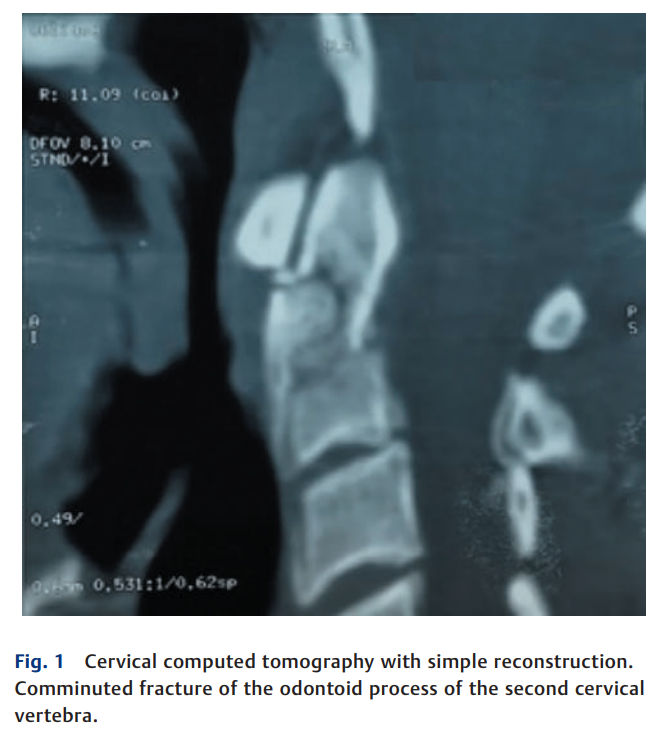

本文介绍一种采用椎板下钢丝的低成本颈椎后路固定技术,用于治疗神经功能完好的年轻患者粉碎性齿状突骨折(IIA型),重点探讨该技术在无法获得先进器械的资源有限环境中的适用价值。